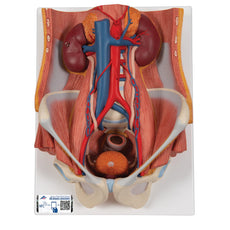

Dual Gender Urinary System, 6-part - Includes 3B Smart Anatomy

This Urinary System all-in-one-model shows:- Structures of retroperitoneal cavity

- Large and small pelvis with bones and muscles

- Inferior vena cava

- Aorta with its branches including iliacal vessels

- Upper urinary tract

- Rectum

- Kidney with adrenal gland.

One front half of a kidney is removable from the anatomical model of the urinary system. With easy to change male insert (bladder and prostate, front and rear half) and female insert (bladder, womb and ovaries, 2 lateral halves) the Urinary System model is a great teaching tool.

Dual Sex Urinary System model on baseboard.